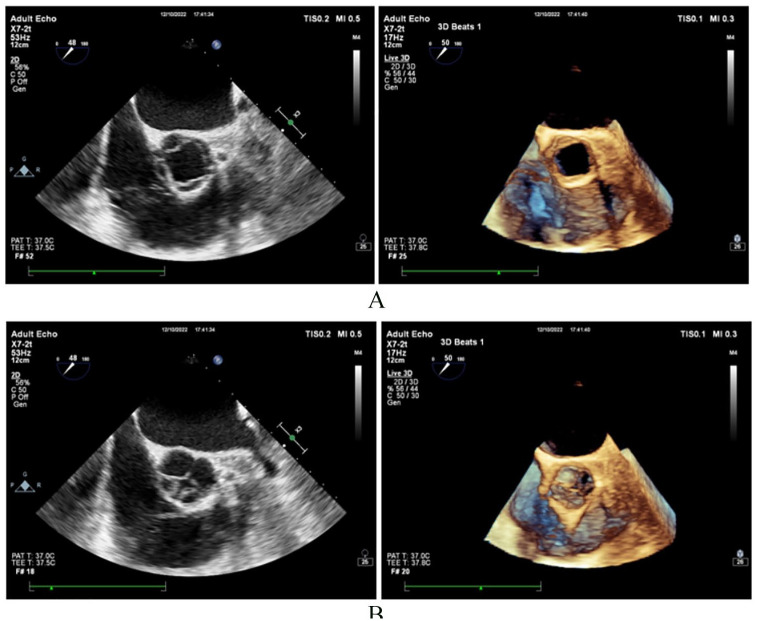

Quadricuspid aortic valve is a very rare congenital anomaly. Its association with rheumatoid arthritis is exceptional with this being the third case reported in the literature. We report a case of a 52 year old female patient with quadricuspid aortic valve type C accompanied by moderate to severe aortic regurgitation and longstanding, advanced form of rheumatoid arthritis. Having refused surgical aortic valve intervention 4 years ago, the patient is currently under a watchful follow-up strategy. The patient received a diagnosis of rheumatoid arthritis over 15 years before and presently has serious deformities in the hands, legs, feet, and spine. In conclusion, quadricuspid aortic valve and rheumatoid arthritis together are extremely rare. While it is possible that this association is coincidental, considering the genetic background of both disorders, there is a potential for them to be interconnected comorbidities. This report is the first to highlight the association between the 2 disorders.

四尖瓣主动脉瓣是一种非常罕见的先天性畸形。它与类风湿性关节炎的关系非常特殊,这是文献中报道的第三例。我们报告了一例 52 岁女性患者的病例,她患有四尖瓣主动脉瓣 C 型,伴有中重度主动脉瓣反流和长期晚期类风湿性关节炎。4 年前,患者拒绝接受主动脉瓣手术治疗,目前正处于观察随访阶段。患者在 15 年前被诊断出患有类风湿性关节炎,目前手、腿、脚和脊柱严重变形。总之,四尖瓣主动脉瓣和类风湿性关节炎同时出现的情况极为罕见。虽然这种关联可能是巧合,但考虑到这两种疾病的遗传背景,它们有可能是相互关联的合并症。本报告首次强调了这两种疾病之间的关联。